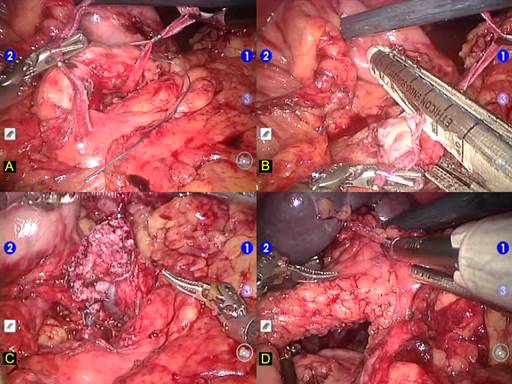

The gastroepiploic ligament and short gastric veins are divided with harmonic scalpel (UltraCision, Ethicon Inc., Cincinatti,OH). This step permits the location and ligation of the splenic artery in the superior border of the pancreas. Posterior aspect of the pancreas at the level of the pancreatic neck is carefully dissected in order to disclose the anterior surface of portal and mesenteric veins. A robotic instrument is inserted behind pancreatic neck and the pancreas is encircled with a cardiac tape. This tape will be used during the whole procedure allowing upward traction of the pancreas (Figure 2a). Next step was to transect the pancreas using a vascular endoscopic stapler (Figure 2b). Once this accomplished, splenic vein is divided with vascular stapler and the distal pancreas is mobilized from the retroperitoneum (Figure 2c). Caution must be taken to control inferior mesenteric vein which runs through the inferior border of the pancreas. The lower pole of the spleen is mobilized through partial division of splenocolic ligament (Figure 2d).

FIGURE 2. Robotic pancreatic resection surgical steps.